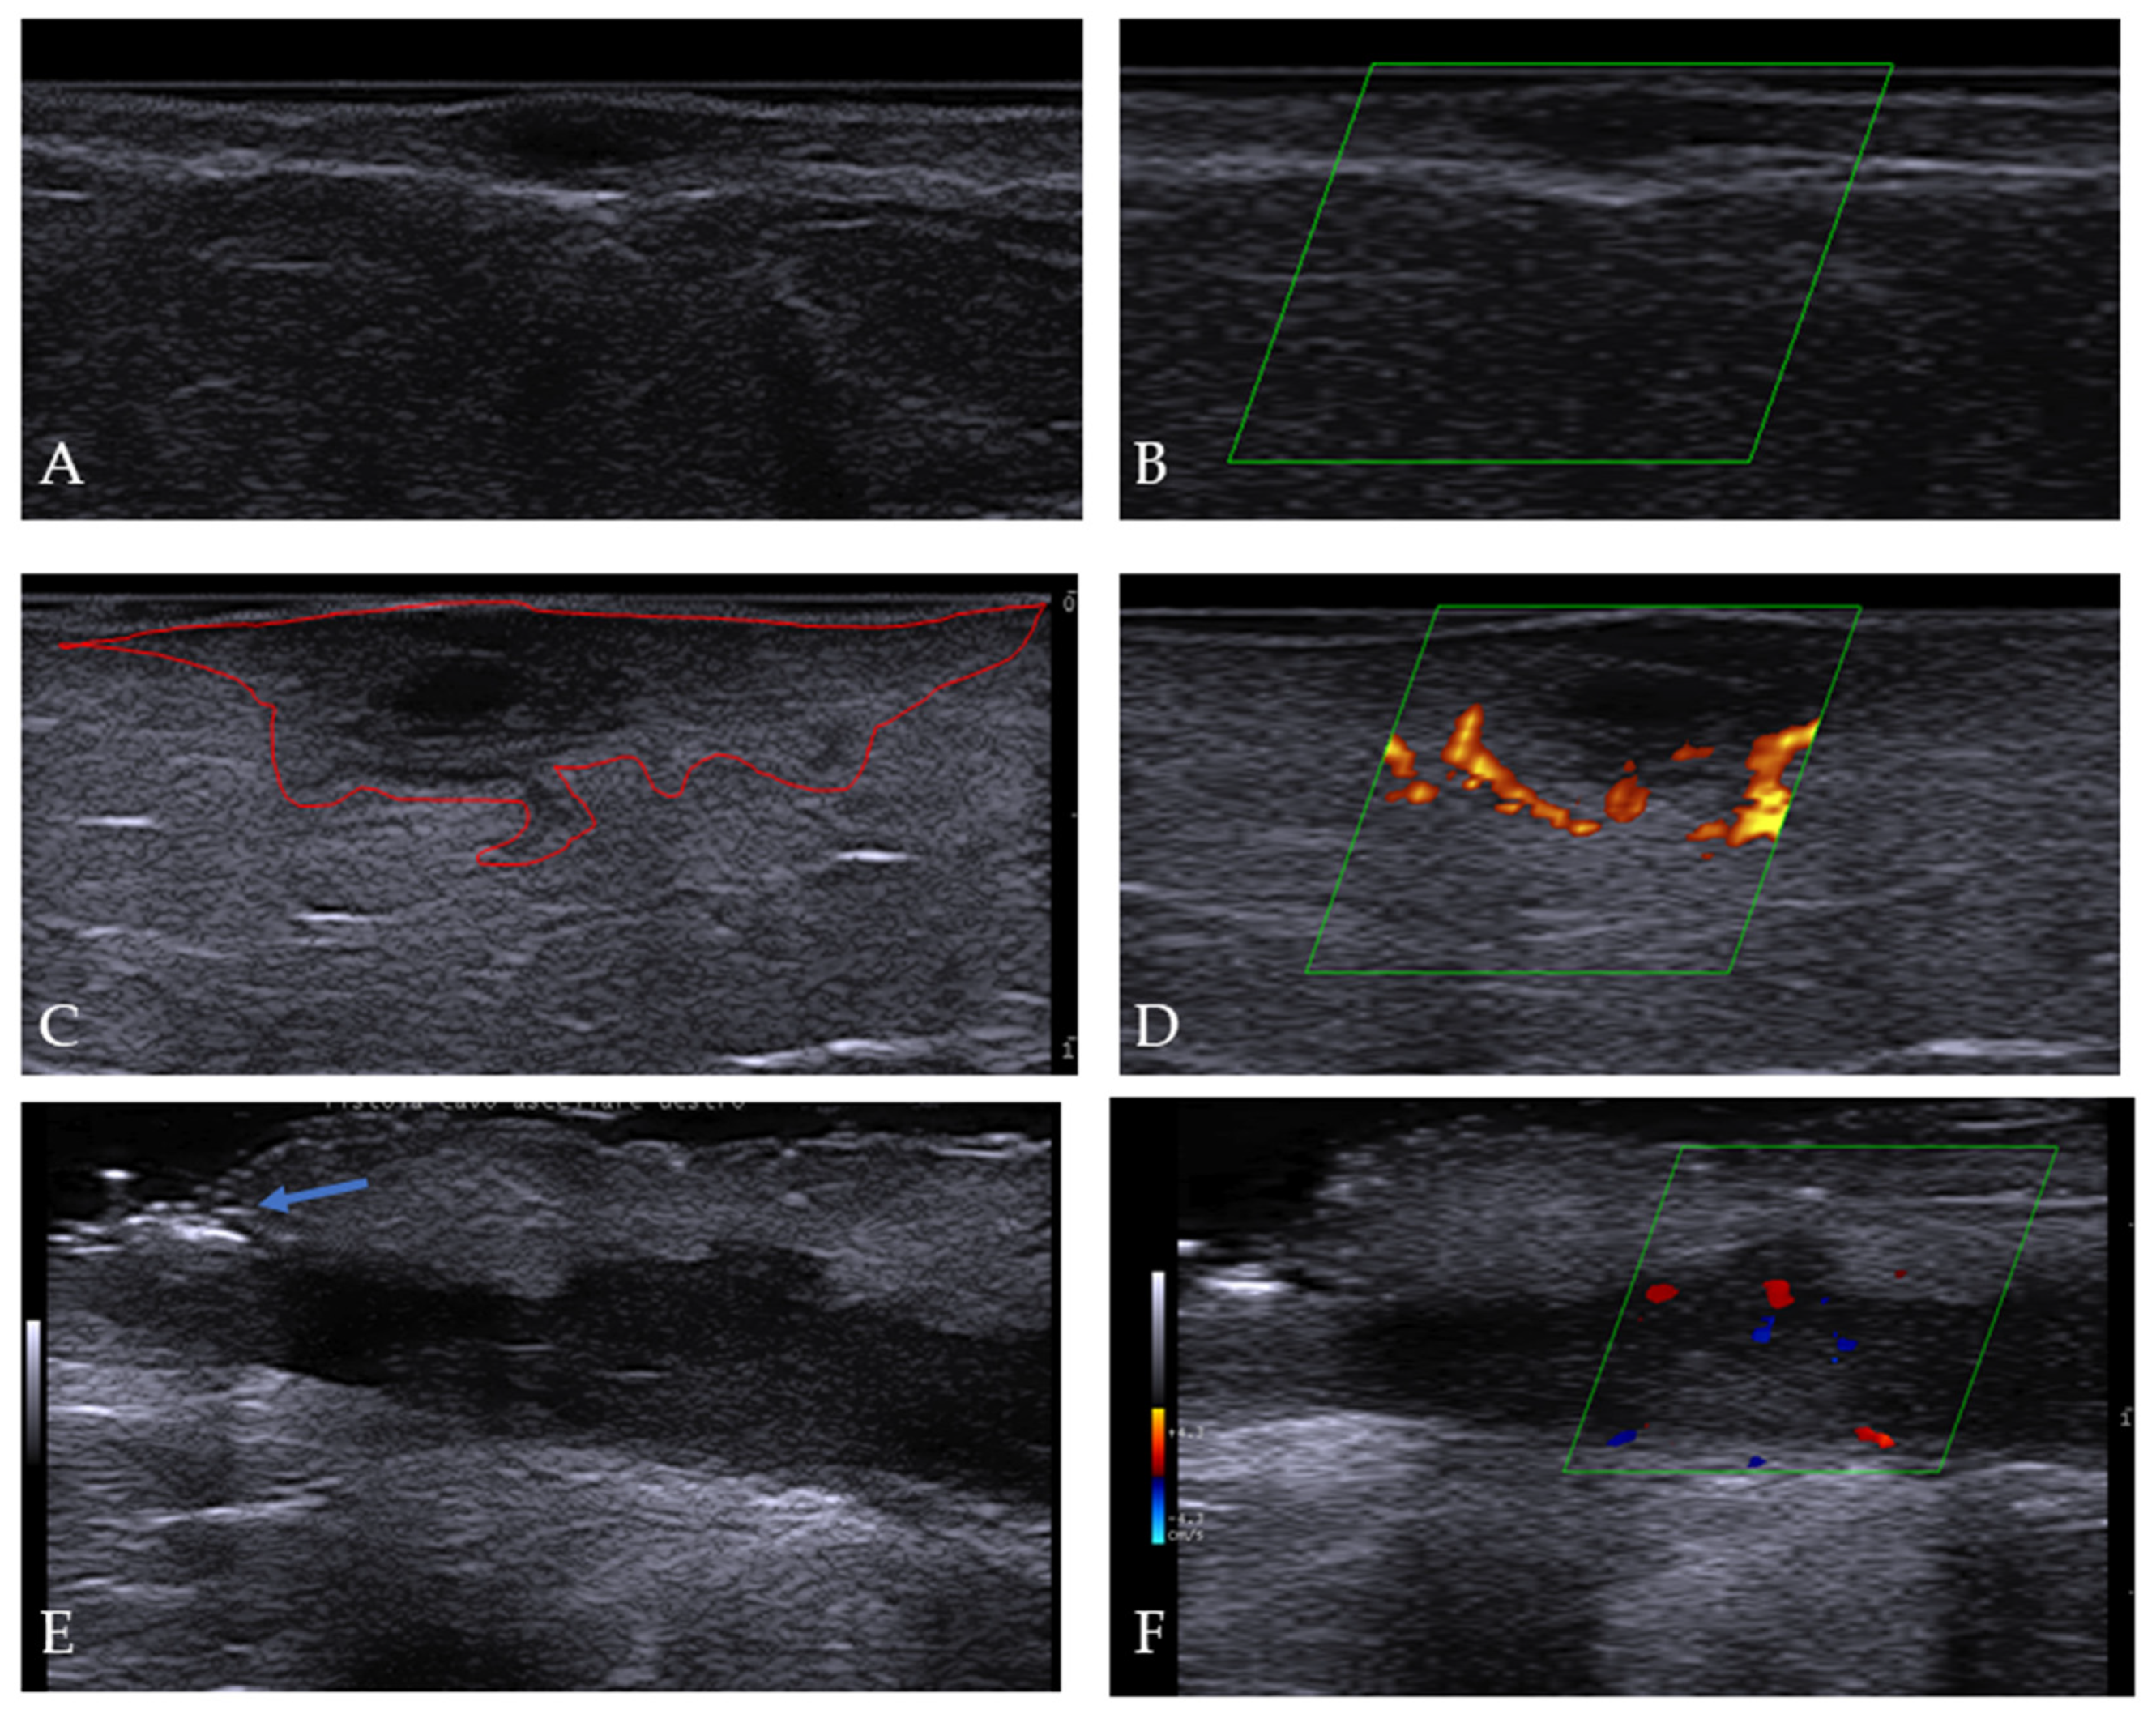

3.4. Ultrasonographic Features